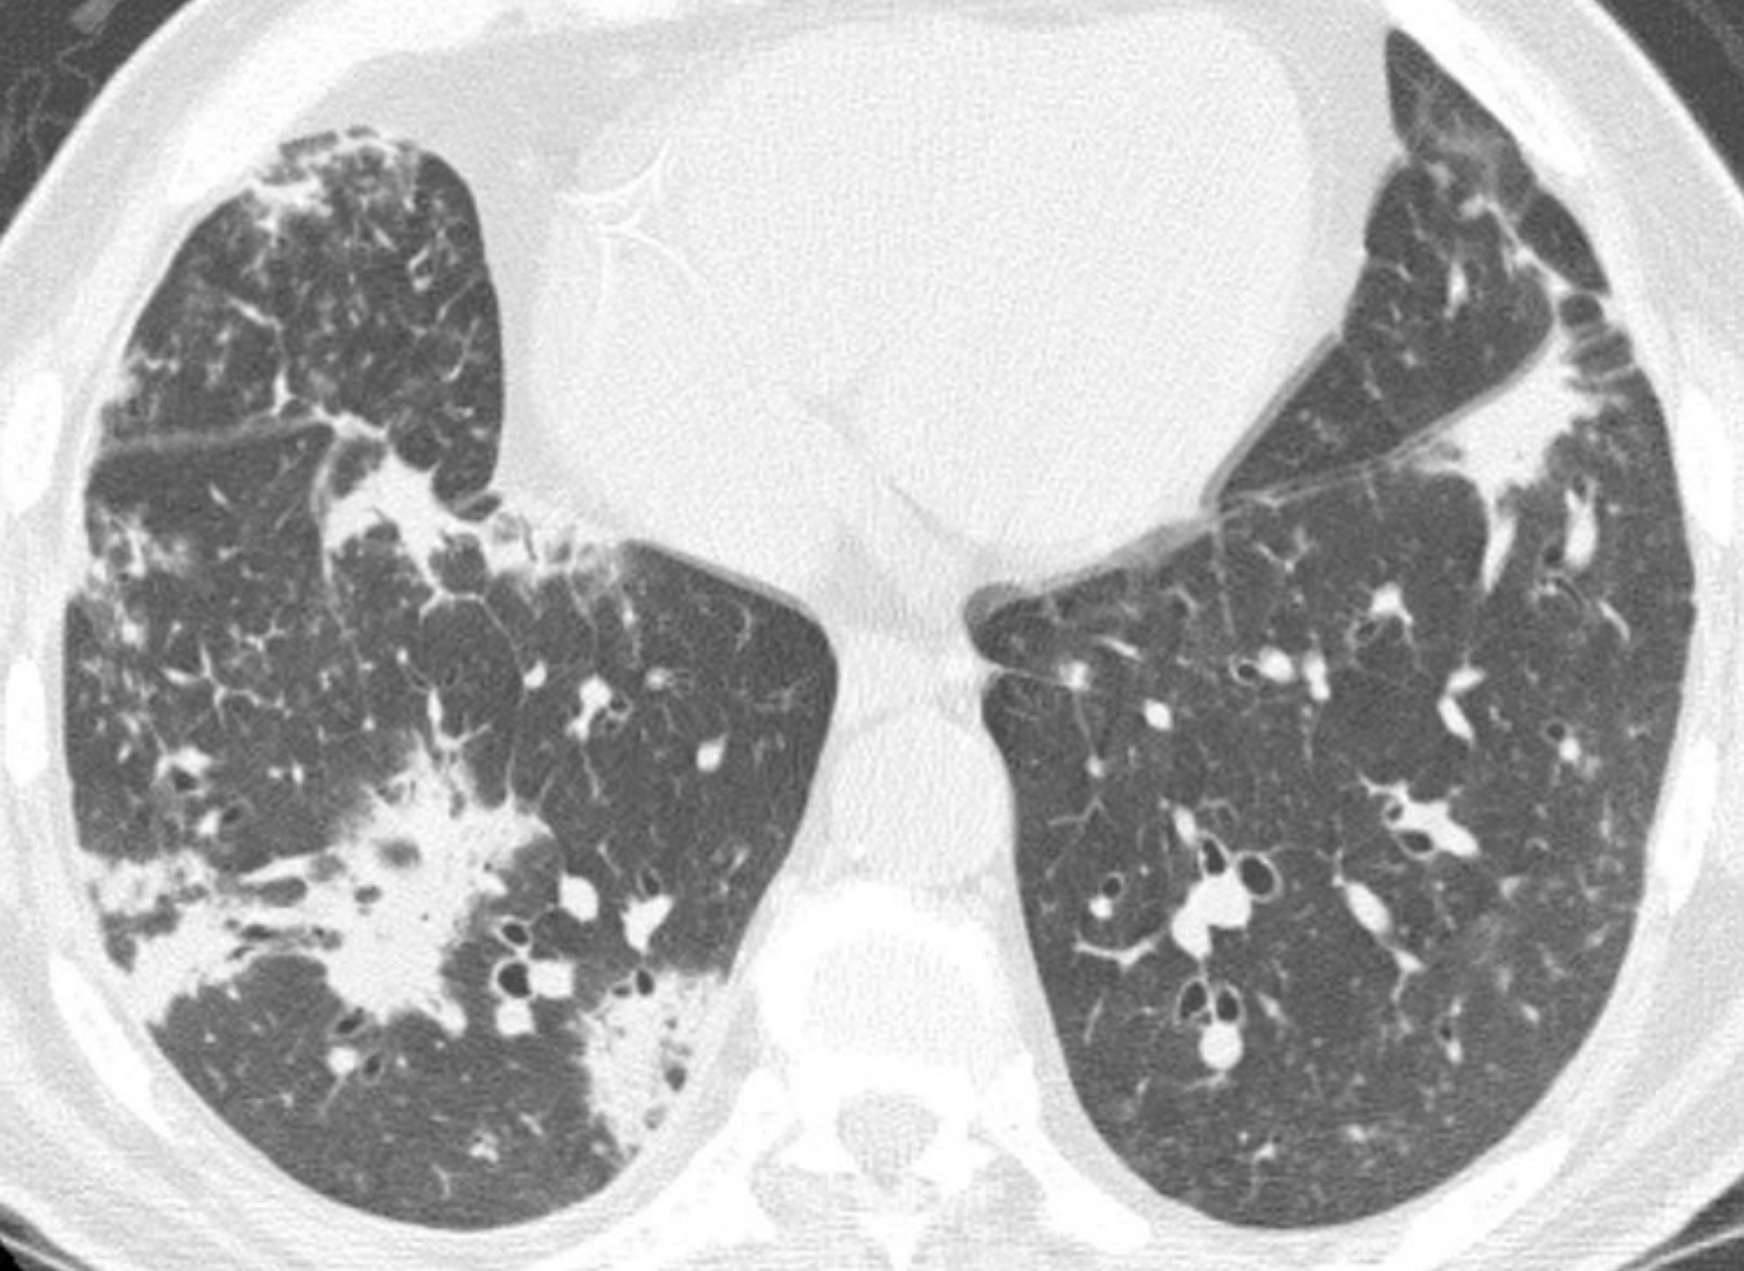

间质性肺炎的HRCT表现取决于炎症或者纤维化的程度。以炎症为主的病例表现为磨玻璃影(GGO)和(或)实变。以纤维化为主的病例表现为不规则网状影、牵拉性支气管扩张和(或)蜂窝征。

虽然在某些病例中可能存在明显的炎症和纤维化成分,但是大部分间质性肺炎通常以两者之一为主要表现。普通型间质性肺炎(UIP)以肺纤维化为主要特征,非特异性间质性肺炎则可能表现为纤维化型或细胞型或两者兼有。其余的间质性肺炎则以炎症为主,但是部分病例可能向纤维化进展。

eb8e21eebff9ef7cc5bf91aa43df6ecf.png

炎症与纤维化的HRCT不同表现。

间质性肺炎表现为不同程度的炎症和纤维化;A和B. 2例结缔组织病患者的非特异性间质性肺炎。

A.HRCT显示GGO,无明显的纤维化征象,提示潜在可逆的炎症性病变;

B.HRCT显示牵拉性支气管扩张(箭)及不规则网状影的纤维化征象,提示对治疗不敏感的肺部瘢痕。